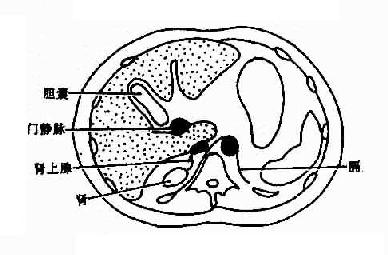

正常肝轮廓光滑,其形状及胸部结构依断面位置而不同。肝门区常有较多脂肪组织,呈不规则形或类似多角形低密度影。其中有肝动脉、门静脉和胆管进出。门静脉较大而居后,肝动脉位于其前内,胆管(主要是肝总管)位于其前外方。增强后门静脉较易识别,呈圆形高密度影,位于下腔静脉之前。CT上易于区分肝的各叶,即左呈、方叶、右叶和尾叶。左叶和方叶以圆韧带裂(又称纵裂)为界:方叶与右叶以右切迹和胆囊窝为界;横行的静脉韧带裂更明显。将左叶与尾叶分开;尾叶与右叶相连,突向内侧,位于下腔静脉的前方,易于识别。不同层面肝的解剖结构见图4-3-4。

图4-3-4 肝不同层面CT表现